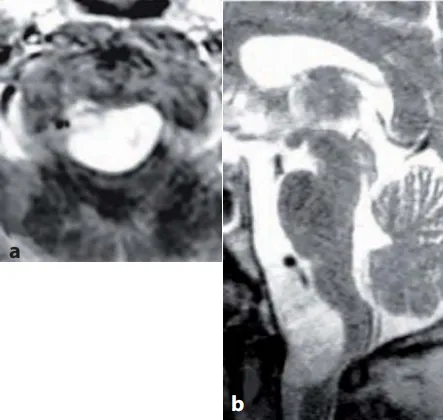

图13.13 a,b术前MR图像(T1-W增强扫描,b矢状T2-W)显示一个大的枕大孔脑膜瘤,该脑膜瘤向背侧生长,严重压迫颈髓。c、图示硬脑膜切开,肿瘤的背外侧和腹侧部分暴露,通过侧面反射硬脑膜和椎动脉的远端V3部分。